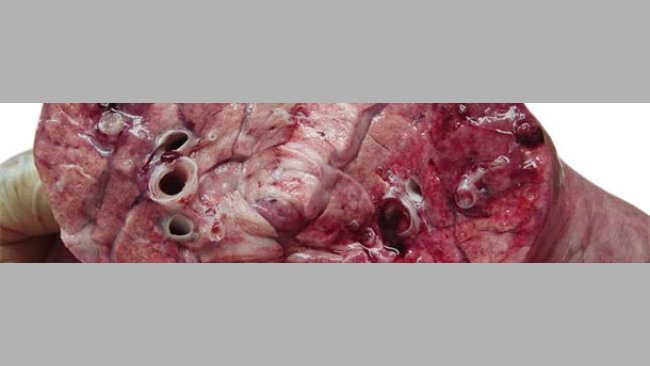

在育肥舍,可见慢性咳嗽和呼吸困难,病猪对抗生素治疗无效,死亡率是8%。